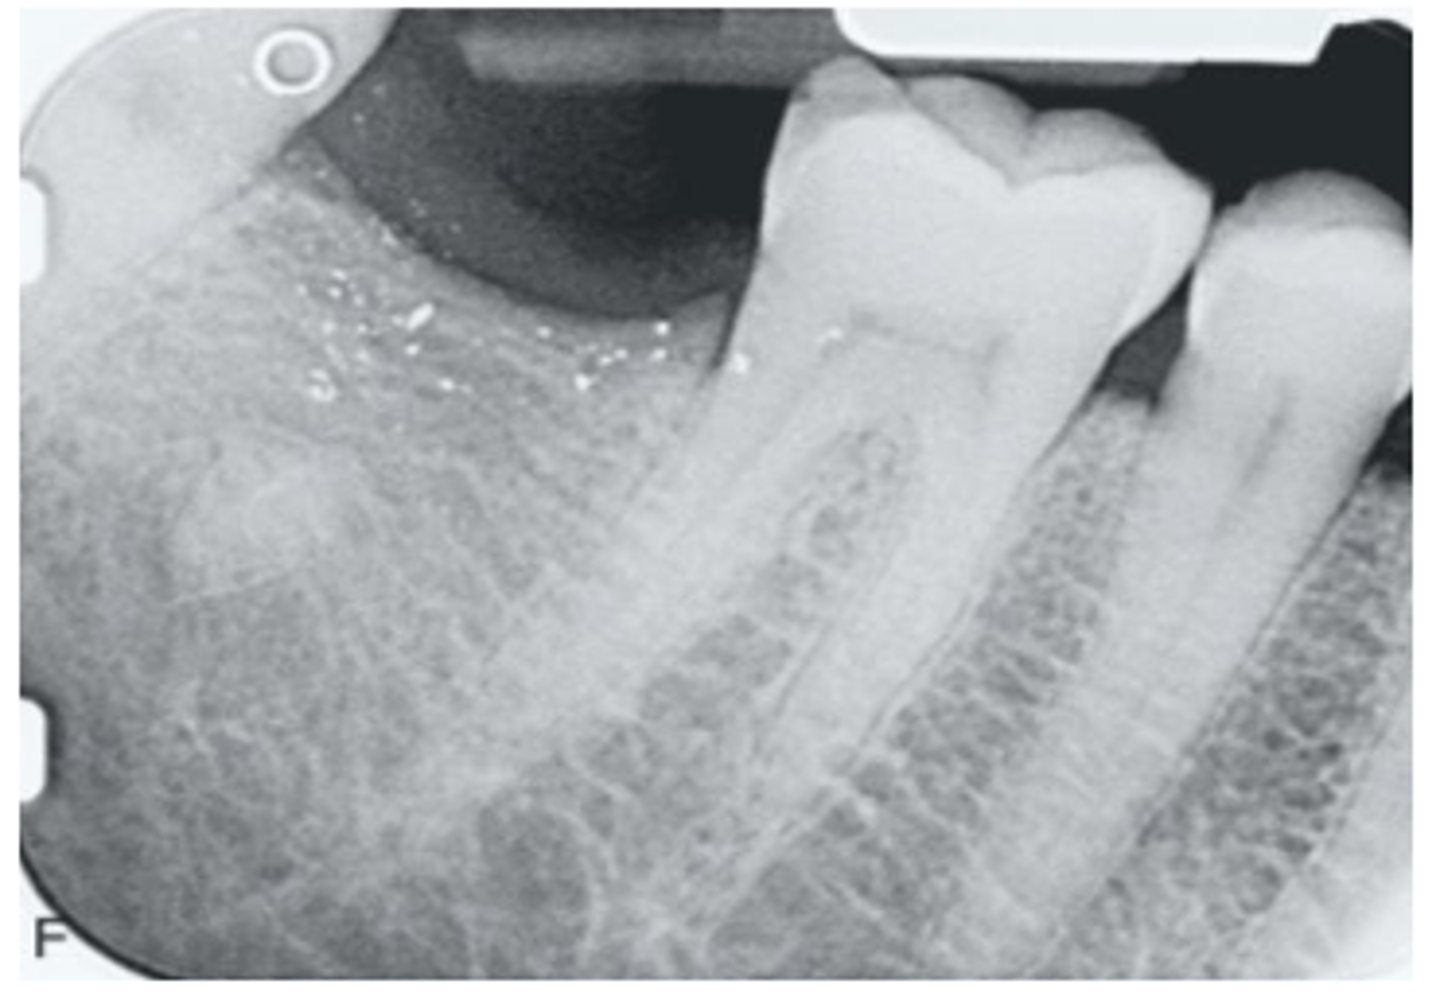

What are the arrows pointing to?

amalgam tattoo

What are the black particles embedded in the purple?

amalgam in scar tissue

These are histopathologic features of what?

- Pigmented fragments

- Staining of reticulin fibers

- Large fragments surrounded by fibrosis

amalgam tattoos